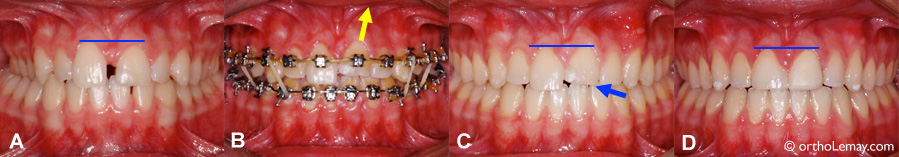

(A et B) La centrale supérieure gauche de cette femme de 43 ans est plus courte et plus basse que celle de droite et le contour de la gencive est très inégal et inesthétique. De plus, elle a une couronne épaisse qui visait à camoufler une rotation importante. (flèche bleue). (C et D) Après l’orthodontie, la position des incisives fut corrigée de façon à harmoniser le niveau de la gencive et permettre au dentiste généraliste de faire une nouvelle couronne mieux proportionnée et plus esthétique.

Mouvements orthodontiques pour harmoniser des incisives de longueur inégale et le niveau de gencive

Utilisation de mouvements orthodontiques pour harmoniser le niveau de gencive des centrales et permettre au dentiste de faire une restauration plus esthétique après le traitement d’orthodontie.